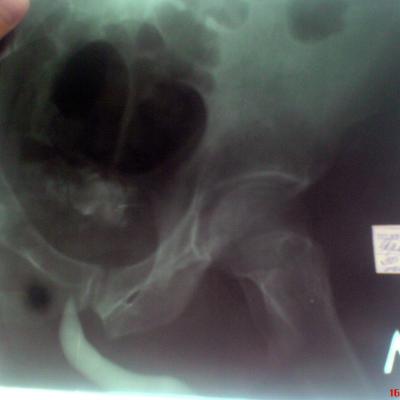

Возможно у Вас проконсультироваться таким образом,я вышлю Вам снимки уретрограмм а Вы скажете свое мнение.